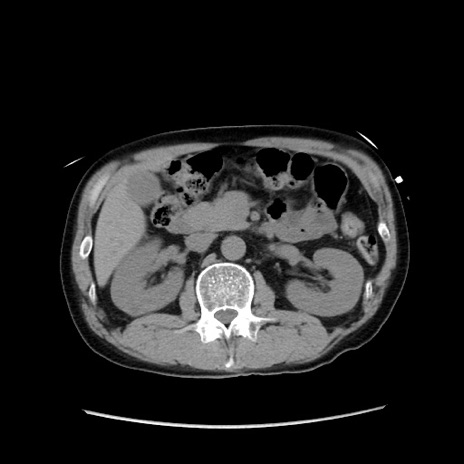

症例37(横断像)

【症例】40歳代 男性

【主訴】腹痛

【現病歴】4時間ほど前に電車に乗車中に臍部上より腹痛出現。徐々に増悪し起立困難となり、救急外来受診。生ものは数日食べていない。今朝お雑煮を食べた。

【身体所見】BT 36.8℃、BP 117/84mmHg、HR 91/min、SpO2 97%、苦悶様、腹部:臍上部広範囲圧痛あり、反跳痛±

【データ】WBC 8100、CRP 0.03